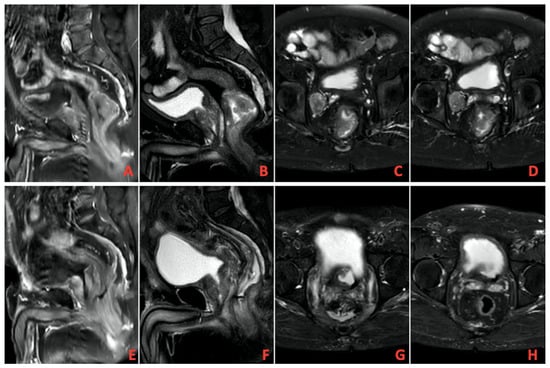

A total of 13 patients evaluated as cCR after TNT was completed were followed up with NOM. Figure 1 shows MRI images of a patient with complete response, and Figure 2 shows PET/CT images. It shows that 39 patients underwent surgery, and 8 of them had pCR. A total of 9 patients had ypT0 (one of them was ypT0N1), 1 had ypT1, 6 had ypT2, 21 had ypT3, and 1 had ypT4. In addition, 27 patients had no pathologically involved lymph nodes (ypN0), 9 had ypN1, and 2 had ypN2. These findings and tumor regression grading distribution are summarized in Table 3.

Figure 2. (AD) Pretreatment imaging, (EH) posttreatment imaging on positron emission tomography/computed tomography (PET/CT).